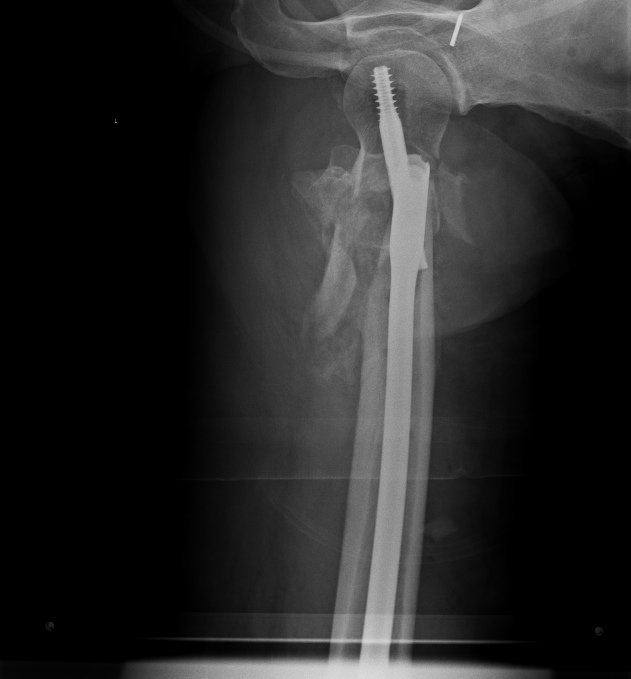

Спасибо за интересное обсуждение. Действительно, головка сохраняет сферичность, кровоснабжение ее должно быть сохранено, так что есть смысл сделать реконструкцию.

Удалили DHS, пришлось вытащить единым блоком, винт прокручивался. . Опознавательных знаков на имплантате не обнаружили. Дополнительный винт был введен во фрагмент, который оказался не связан ни с чем, так что удалили и его После удаления была хорошая подвижность. Сделали остеосинтез вот так. Комментарии и критика приветствуются.